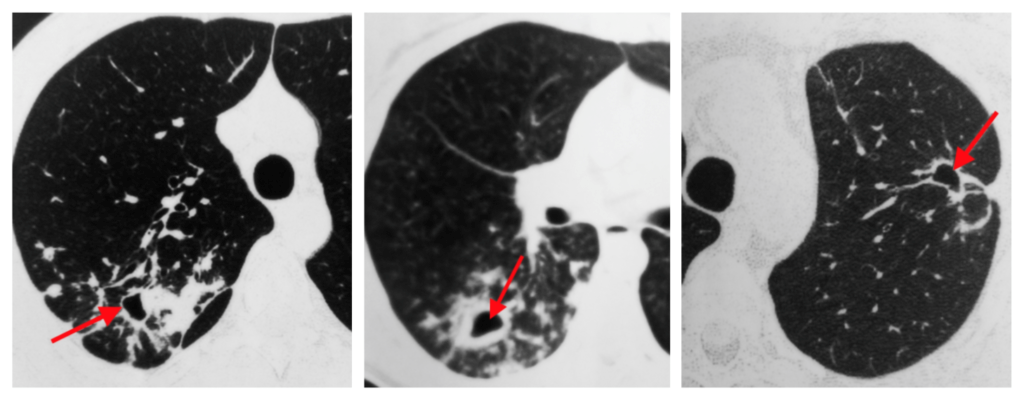

- Mediastinal strukturlara yayılmanı dəqiqləşdirmək üçün KT və endobronxial USM ilk seçimdir (Şəkil 11).

Şəkil 11. Ağciyər xərçənginin diaqnostikası (KT).